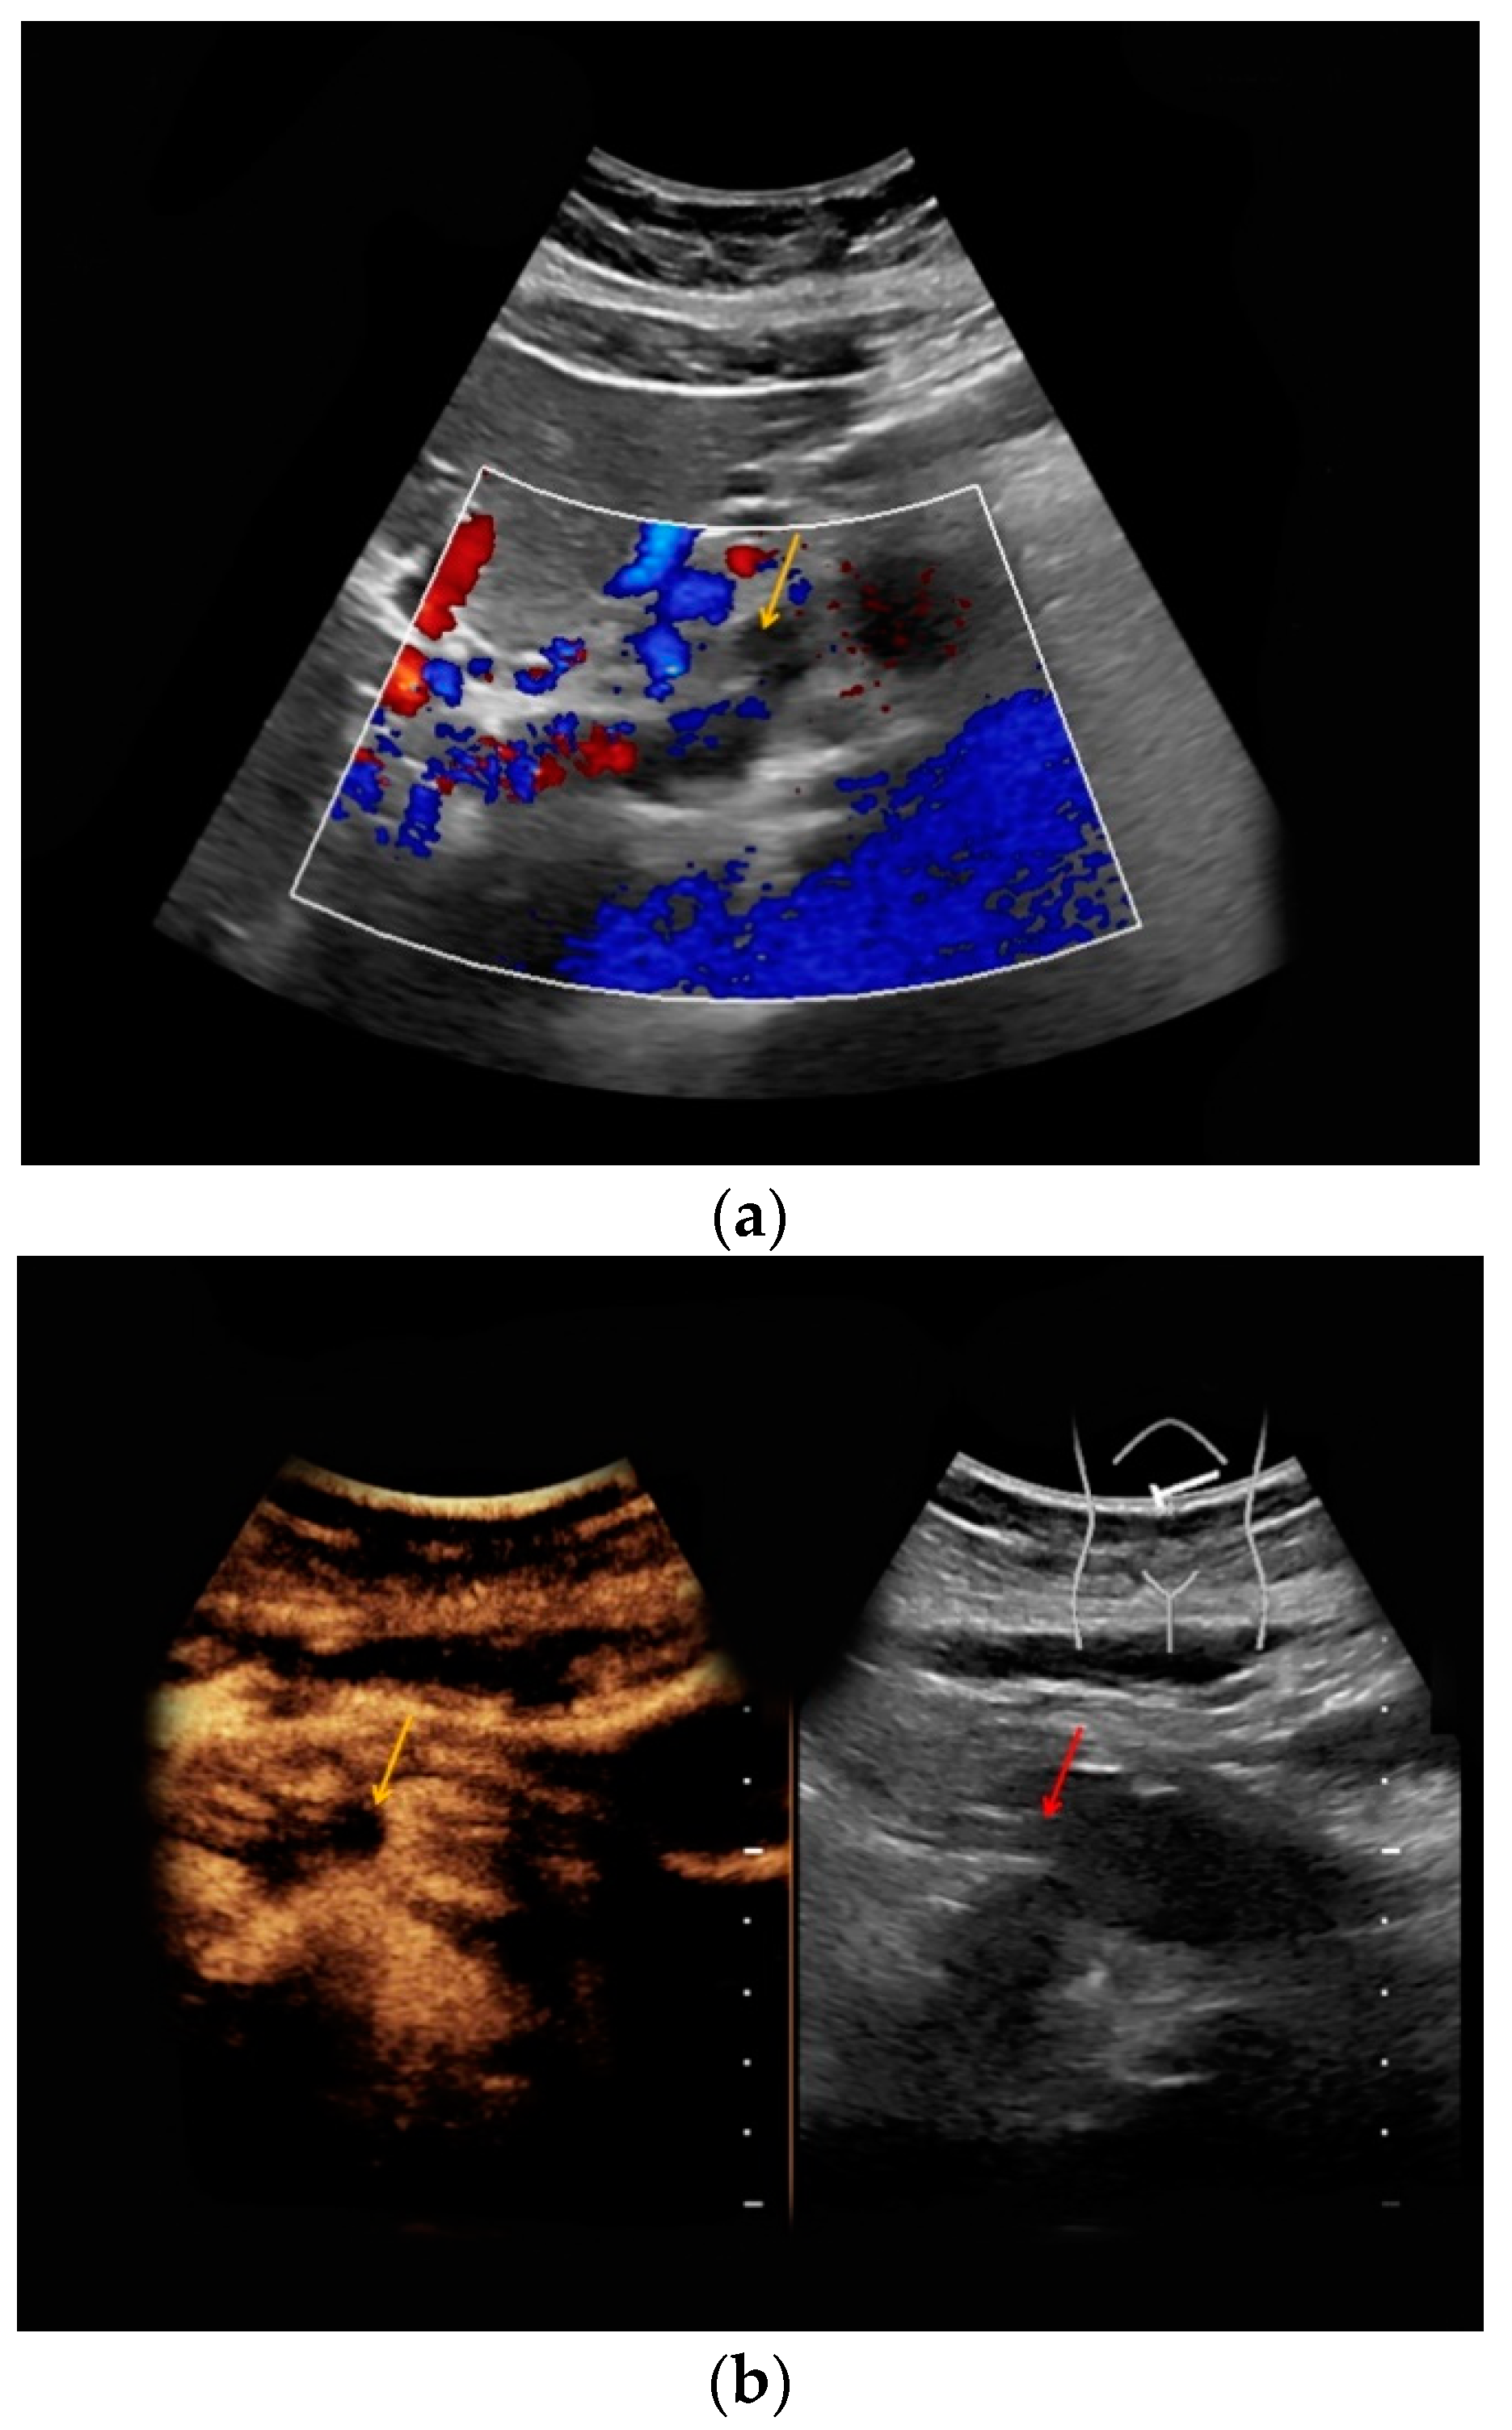

| #2 | 37 | 21 | Pyelonephritis, ruled out the presence of an abscess | B-mode: no abnormalities Doppler: no abnormalities CEUS: homogeneous contrast enhancement, no abscess | homogeneous, restricted diffusion, perirenal fluid collections |